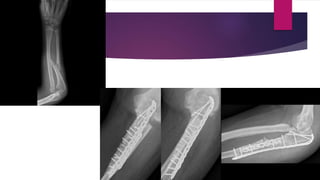

FRACTURE OF THE RADIAL SHAFT AND DISLOCATION OF THE DISTAL

RADIOULNAR JOINT (GALEAZZI FRACTURE-DISLOCATION)

 Displaced fractures of the distal third of the radial shaft are not common, but when they do

occur, they are associated with complete disruption and dislocation of the distal radioulnar

joint

 In this injury, which is usually sustained by young adults, the distal fragment of the radius is

tilted posteriorly (anterior angulation at the fracture site)

 The carpus and hand are displaced with the radius and the resultant clinical deformity is

striking

 Radiographically, the nature of the fracture-dislocation is most apparent in the lateral

projection

 The optimum form of treatment for the Galeazzi fracture-dislocation is open reduction and

internal fixation of the radius, with either a plate and screws or an intramedullary nail

 When the radius is perfectly reduced , so also is the dislocation of the distal radioulnar joint

reduced

FRACTURE OF THERADIAL SHAFT AND DISLOCATION OF THE DISTAL RADIOULNAR JOINT (GALEAZZI FRACTURE-DISLOCATION)  Displaced fractures of the distal third of the radial shaft are not common, but when they do occur, they are associated with complete disruption and dislocation of the distal radioulnar joint  In this injury, which is usually sustained by young adults, the distal fragment of the radius is tilted posteriorly (anterior angulation at the fracture site)  The carpus and hand are displaced with the radius and the resultant clinical deformity is striking  Radiographically, the nature of the fracture-dislocation is most apparent in the lateral projection

 The optimumform of treatment for the Galeazzi fracture-dislocation is open reduction and internal fixation of the radius, with either a plate and screws or an intramedullary nail  When the radius is perfectly reduced , so also is the dislocation of the distal radioulnar joint reduced